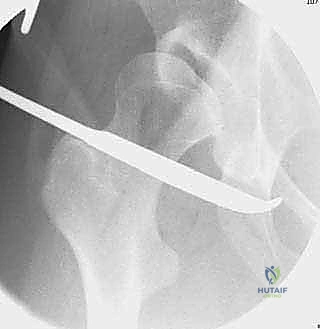

القطع الأول: القطع الإسكي غير المكتمل (Incomplete Ischial Osteotomy)

باستخدام إزميل خاص ذو زاوية (Angled Osteotome)، يتم إجراء قطع في عظم الإسك أسفل الحُق مباشرة (في الأخدود تحت الحُقي). يتم هذا القطع بتوجيه الأشعة السينية (Fluoroscopy) لضمان عدم اختراق المفصل. يحرص الدكتور هطيف على إبعاد العصب الوركي والأوعية السدادية بأمان تام.